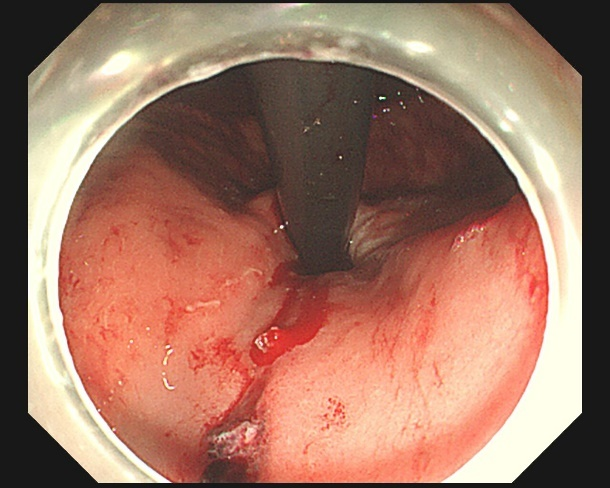

小张病情十分凶险,李琨琨立即为他安排急诊,内镜下,金属夹夹闭止血,术中,李琨琨惊讶地发现,小张醉酒呕吐导致贲门黏膜撕裂,创面居然长达 10 公分,局部可见裸露血管,并活动性出血。

可见小张呕吐的力道有多大!

李琨琨技术娴熟的为创面一一打上金属夹,就好像把伤口针针缝合住一样,止血效果立竿见影,小张的血压终于稳定!